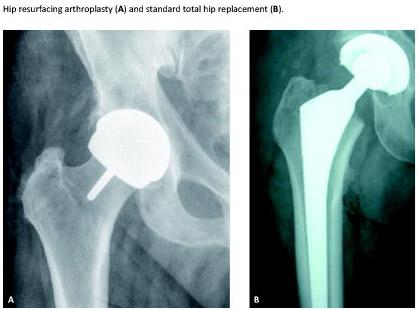

During the past decade, hip resurfacing arthroplasty (HRA) has been used in selected Danish patients with degenerative hip disease [1]. HRA is used mainly in cases where younger patients might otherwise be expected to replace their standard prosthesis within 10-15 years. The procedure consists of placing a hollow, mushroom-shaped metal cap over the femoral head while a matching metal cup is placed in the acetabulum (pelvis socket). HRA may have some advantages compared with conventional total hip replacement (THR). Resurfacing surgery preserves more femoral bone than conventional THR surgery which preserves the option of further treatment via a standard THR. Register studies show an overall increased failure rate of HRA compared with THR, but in male patients younger than 65 years with primary osteoarthritis, the survival rates of HRA are equivalent to those of THR [2, 3]. The internationally recommend age group for HRA prosthesis is younger patients [4].